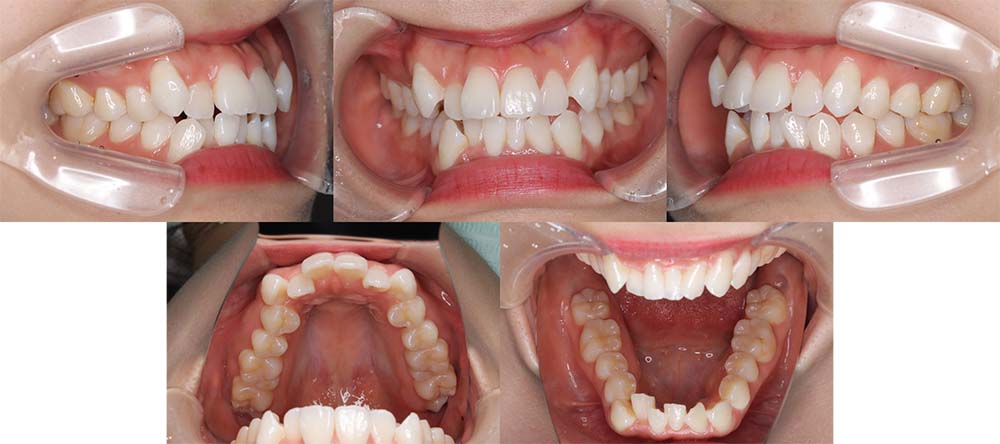

| 症例分類 | 上顎前突、叢生、シザースバイト |

| 診断名 | 右上7のシザーズバイトを伴う上下重度叢生skeletal2 |

| 主訴 | 歯並びが悪くて全体的にガタガタ |

| 年齢 | 19歳11ヶ月 |

| 性別 | 女性 |

| 抜歯部位 | 上顎左右と右下の第一小臼歯、左下の第二小臼歯(4本)、上顎右側第二大臼歯 |

| 使用装置 | 裏側のワイヤー装置 |

| 治療期間 | 2年11ヶ月(5ヶ月程度来院出来ない期間あり) |

| 保定装置 | 固定式保定装置、取り外し式保定装置(8時間) |

| 費用 |

[検査・診断料] ¥49,500 [基本施術料] ¥1,331,000 [調整料] ¥5,500/回 [抜歯] ¥5,500/本 [保定装置] ¥55,000(税込) 抜歯や虫歯治療は他院にて費用が別途かかります。(抜歯¥4,000〜10,000/本)

上下の重度叢生と上の歯が前方にあり上顎両側の第一小臼歯と下顎右側第一小臼歯、下顎左側第二小臼歯、上顎右側第二大臼歯(上顎右側親知らずを咬合に使用)を抜去して上下リンガルで治療を行いました。 左上の第二大臼歯部の咬合が深かったため、一時的に頬側に装置をつけさせて頂きました。裏側に装置を装着すると噛み合わせを浅くするためのバイトアップがかなりの量が必要になり咬みづらくなってしまうためです。

5ヶ月程度来院が出来なかった期間がありましたが、問題なく治療を終了することができました。